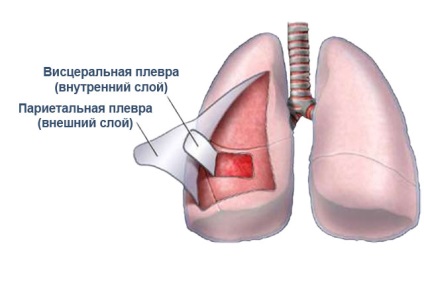

A kapcsolat a mellhártya lemezek.

Így a lapokat lehet kialakítani pleurális plakk, amely elsődlegesen fibrin szerek: ilyen esetben nevezzük fibrines pleuritis vagy száraz. Vagy van egy növekedés folyadékkibocsátás, azaz, a formáció a folyadékgyülem a mellhártya üregbe, és csökkenti annak abszorpciós mellhártya: mellhártyagyulladás ebben az esetben az úgynevezett váladékos vagy exszudatív. A normál állapotban mellhártya lemezek készített mintegy 1-2 ml folyadék, amely egy sárgás színű, és némileg hasonló összetételű a plazma - a folyadék része a vér. Jelenléte csökkenti a súrlódást mellhártya egymást, és biztosítja a normális légzést.

Reakcióvázlat anatómiája a mellhártya és a tüdő arányok.